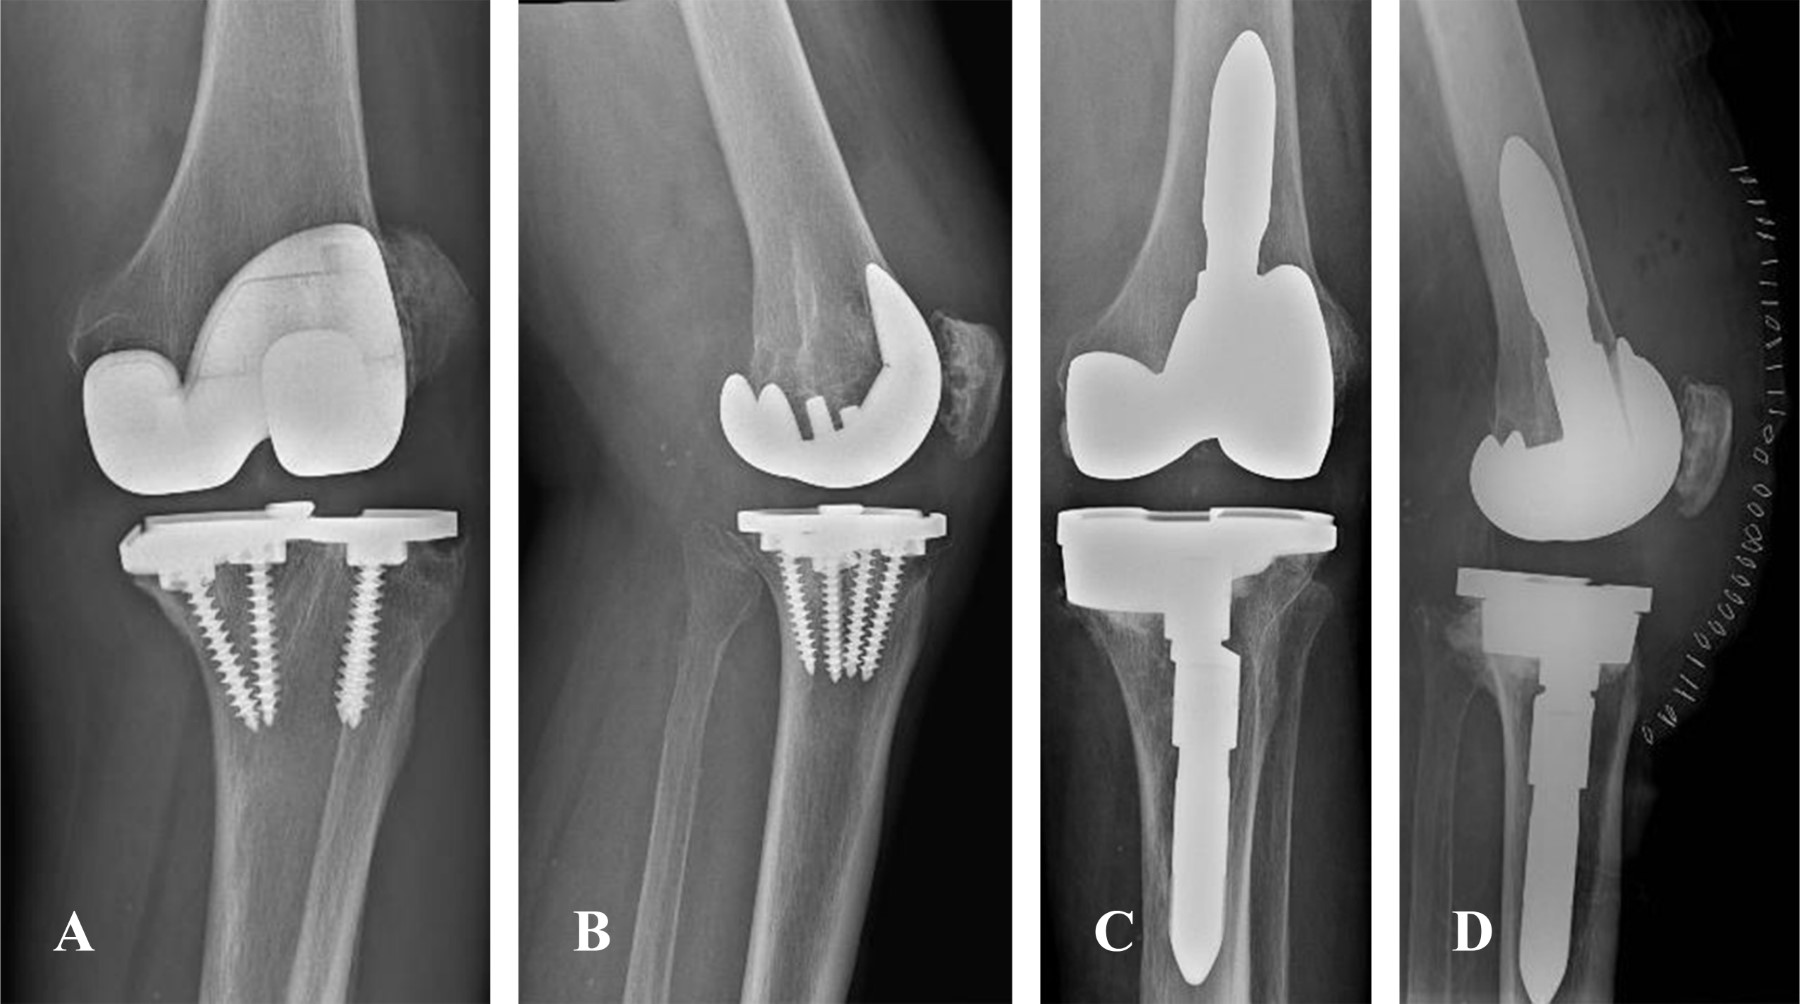

Different types of fixation in revision total knee arthroplasty Fixation In Arthroplasty Achieving adequate implant fixation is critical to optimize survivorship and postoperative outcomes after revision total knee arthroplasty (rtka). This comprehensive review examines the primary fixation methods (cemented, cementless, and hybrid fixation),. The current literature indicates no major superiority of using a specific stem fixation method for revision total knee arthroplasty. Despite improved survivorship of uncemented fixation in total knee arthroplasty.. Fixation In Arthroplasty.

Different types of fixation in revision total knee arthroplasty Fixation In Arthroplasty Despite improved survivorship of uncemented fixation in total knee arthroplasty. In revision total knee arthroplasty (rtka), one of the critical considerations is the method of stem fixation, which plays a major. Achieving adequate implant fixation is critical to optimize survivorship and postoperative outcomes after revision total knee arthroplasty (rtka). Over 100,000 total knee replacements (tkrs) are carried out in the. Fixation In Arthroplasty.